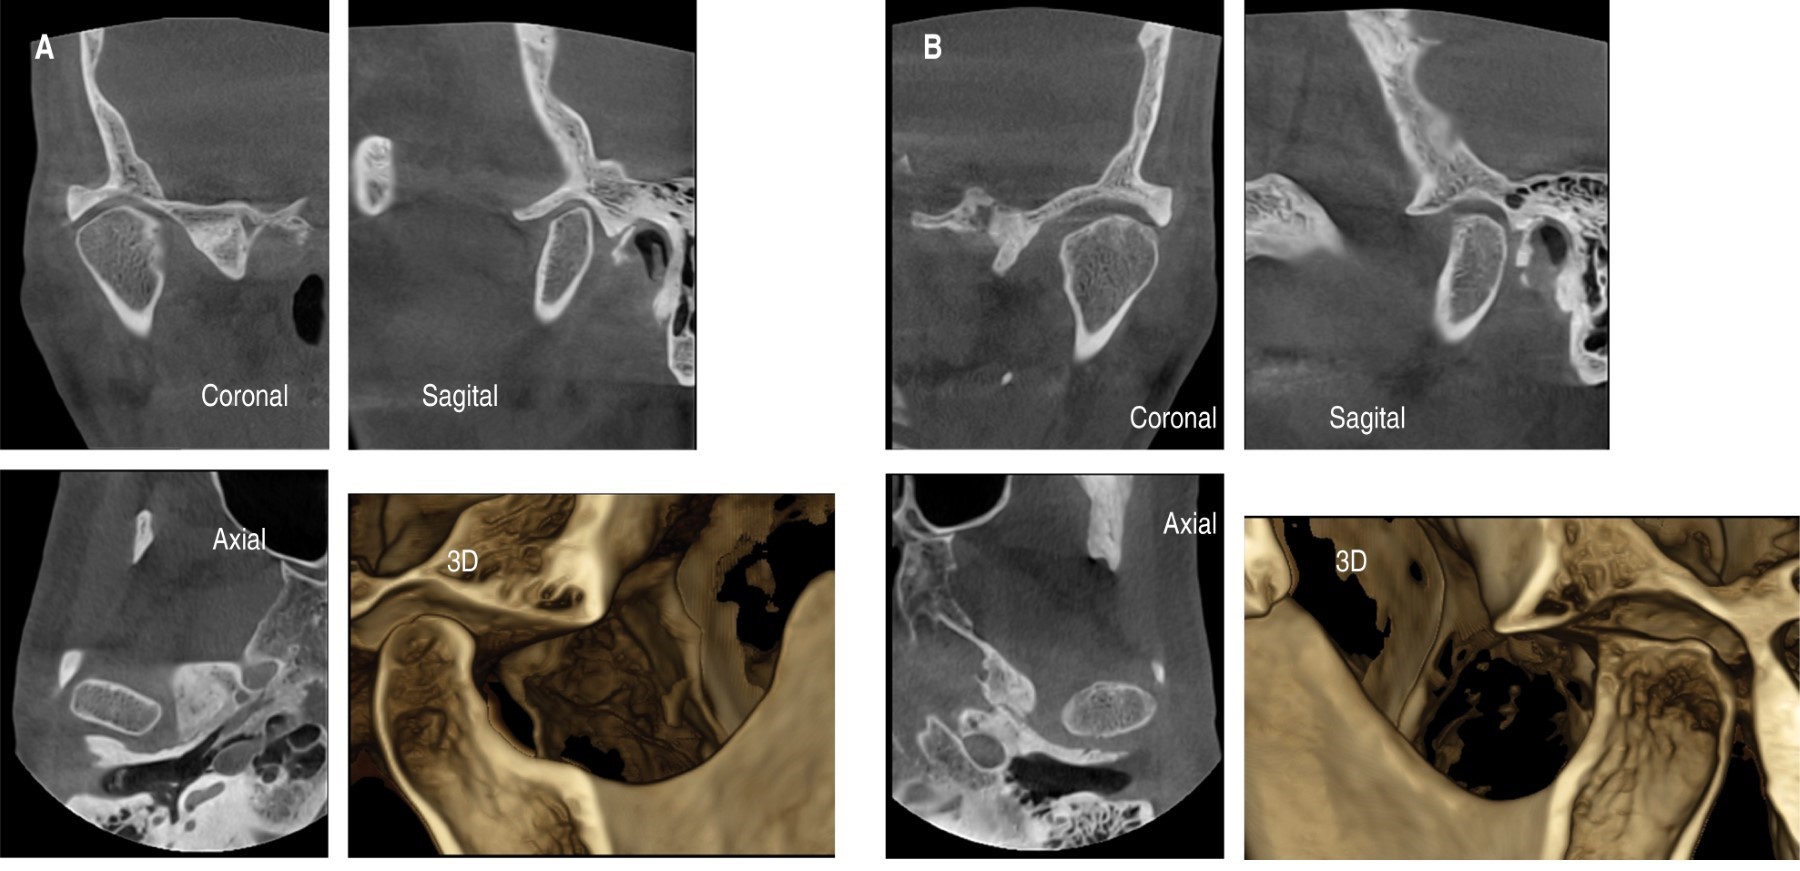

Se solicita resonancia magnética nuclear (RMN) y CBCT sospechando trastorno temporomandibular intracapsular (Figuras 3 y 4).

En la RMN se observa una lesión en la apófisis coronoides del lado izquierdo (Figura 4). En la ciudad de Bahía Blanca, Buenos Aires, Argentina donde desarrollamos nuestra práctica, no contamos con tomógrafo computarizado de haz cónico de Fov amplio, por lo tanto, se solicita una tomografía computarizada multislice, en la cual se verifica una lesión tumoral en la apófisis coronoides izquierda con forma de hongo, que se introduce entre el arco cigomático y el maxilar desplazando ambas estructuras (Figuras 5 y 6).

Figura 3

Figura 4